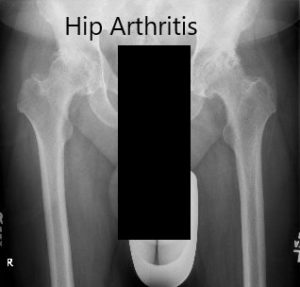

Imaging studies revealed severe bilateral osteoarthritis of the hips with subchondral cysts, sclerosis, and osteophytes. Considering the lifestyle limiting hip pain, she was advised bilateral total hip replacement. She agreed to go ahead with the procedure.

Preoperative X-ray showing the AP view of the pelvis with both the hips.